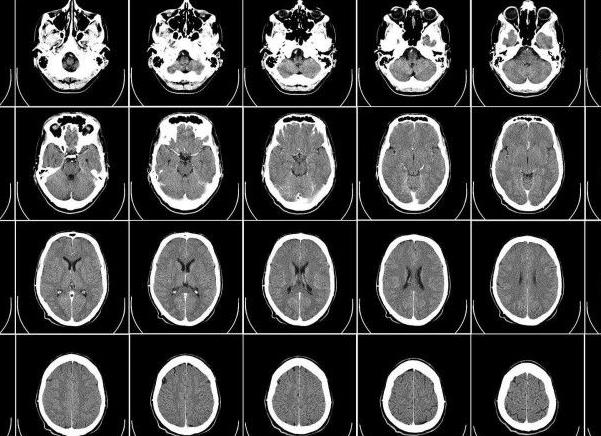

Сегодня существует только один метод, позволяющий диагностировать заболевания головы с точностью 99,9% – магниторезонансная томография. Вопреки бытующим стереотипам, это обследование не несет скрытых угроз для пациента – никакой боли, находясь внутри томографа, он не чувствует и никакого облучения не получает. Все, что от него требуется, – снять с себя все металлические предметы и лежать неподвижно около 40 минут. По итогу ему выдадут на руки комплект МРТ снимков, но которых лечащий врач может рассмотреть мозг под выгодным углом и обнаружить патологию на самых ранних этапах ее развития.

Суть томографии заключается в том, что она позволяет уловить отклики тканей организма, после того, как сквозь них проходят электромагнитные волны. На сегодня это самое информативное и точное обследование, которое способно предоставить информацию относительно состояния внутренних органов. Популярность метода обусловлена тем, что он является безвредным, при этом с его помощью получают трехмерную картинку тканей, сосудов, нервов. Благодаря 3D изображению головного мозга очаг патологии выявляют очень быстро, он виден до мельчайших деталей.

Обзорная томография может показать доктору максимум информации, благодаря объемной картинке. Она выявляет внутренние кровотечения. Врач внимательно рассмотрит процессы перемещения внутримозговой жидкости и крови, после чего диагностирует наличие или отсутствие патологии.

Самым важным элементом аппарата является магнит большой силы, который создаёт вокруг пациента мощного магнитного поля. Специальная компьютерная система регистрирует появление импульсов, имеющих высокую частоту, в каждой из клеток головной части человеческого организма. Можно проводить с помощью этой разновидности исследования и определение других частей тела. На экранной поверхности можно увидеть изображение структуры мозгового отдела головы и сосудистой области.

Специалистом полученные снимки расшифровываются. Они распечатываются или передаются лечащему врачу в электронном виде, который на основании этого при необходимости назначает лечение.

Наибольшую сложность исследования представляет собой работа по расшифровке результатов. Сам пациент это сделать не может. Снимки, которые получены в ходе исследования, внимательным образом должны быть изучены специалистами. Если у пациента идёт развитие какого-либо недуга, то на снимках это можно увидеть.

Если в головном мозге есть новообразование, но на снимке оно выглядит в виде светлых пятен с ассимметричными краями, которые сразу же видны, так как имеют большую яркость.

При инсультных проявлениях на снимке можно увидеть светлое пятно. При исследовании, которое проводилось с воздействием контрастного вещества, снижается циркуляционный процесс в зоне светлого пятна.

При наличии гидроцефалийных болезней можно увидеть на снимке, что расширились желудочки в субарахноидальном и периваскулярном пространстве.

Высветленные области, присутствующие в зоне белого вещества, указывают на рассеянный склероз. Присутствовать такая область может не одна. Аневризменные изменения видны в виде сильного истончения и расширения стенок сосудистой системы.